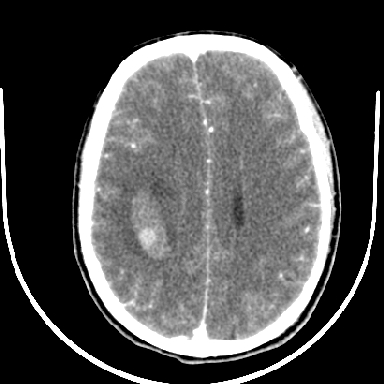

标题: CT6056:脑出血(血管畸形?) [打印本页]

标题: CT6056:脑出血(血管畸形?)

m 40突发头痛左侧偏瘫3小时

考虑高血压性脑出血,依据:

1是高血压性脑出血的好发部位,形态呈肾形,是高血压性脑出血的常见形状

2增强时占位效应加重了,考虑出血还没有停止

3病灶周围水肿不是太厉害,一般肿瘤出血水肿多非常明显

4病灶周围的‘软组织’影没有明显的强化

5至于脑血管畸形引起的出血,暂时没有看到明显的畸形血管影,也不太支持

支持右侧基底节脑出血

右侧基底节区脑出血.

支持右侧基底节区(主要为外囊区)原发性脑出血。

另附部分资料:“血液溢出血管外形成血肿,其内含有大量血红蛋白、血浆白蛋白,球蛋白,因这些蛋白对x线的吸收系数高于脑质,故ct呈现高密度阴影,ct值达40~90h,最初高密度灶呈非均匀一致性,中心密度更高,新鲜出血灶边缘不清。基底节区血肿多为“肾”型,内侧凹陷,外侧膨隆,因外侧裂阻力较小,故向外凸,其它部位血肿多呈尖圆形或不规则形”

术中抽出40ml陈旧血液,血肿底部似见一条索血管影